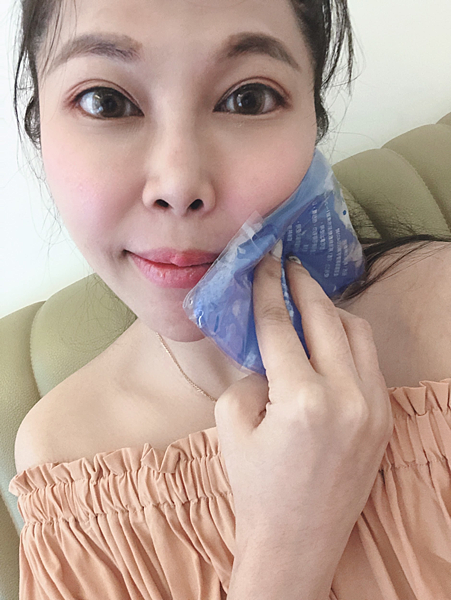

除了刚开始听到电钻的声音我真的很害怕,但后续包含手术中切牙肉跟缝线整个过程都会不会感觉到疼痛~只能说医师的技术真的非常好呀!!

在补完骨粉后,护理人员会很清楚的解释拔牙补骨粉后需要的注意事项。

我自己觉得李医师的技术非常好 ,整个过程我没有感到太大不舒服跟疼痛的地方。但还是有准备止痛药让你觉得需要时可以用~